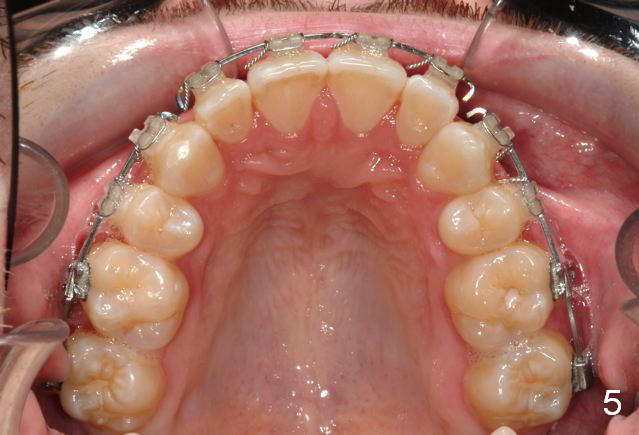

Initial bonding on 08/04/2014 (Fig.1-3); follow up appointments (09/20/2014 (Fig.4,5); 11/11/2014 (Fig.6,7), prepared for maxillary segmental surgery to expand, advance, and level.

I routinely start off with a round NiTi AW, like .014 in the .018 slot, then to .016 and up to 16X22 NiTi. Then I go to rectangular SS.  I segmented the AW to facilitate the surgery.

What is advantage to segment AW initially (in the 1st appointment of bonding, Fig.1,2)?

Avoids compensating teeth and building in instability in a surgery case.

A continuous AW would align AND 'level'. The rule is never move teeth before surgery in a direction they will be corrected at the time of surgery. This concept we may need to talk in person.